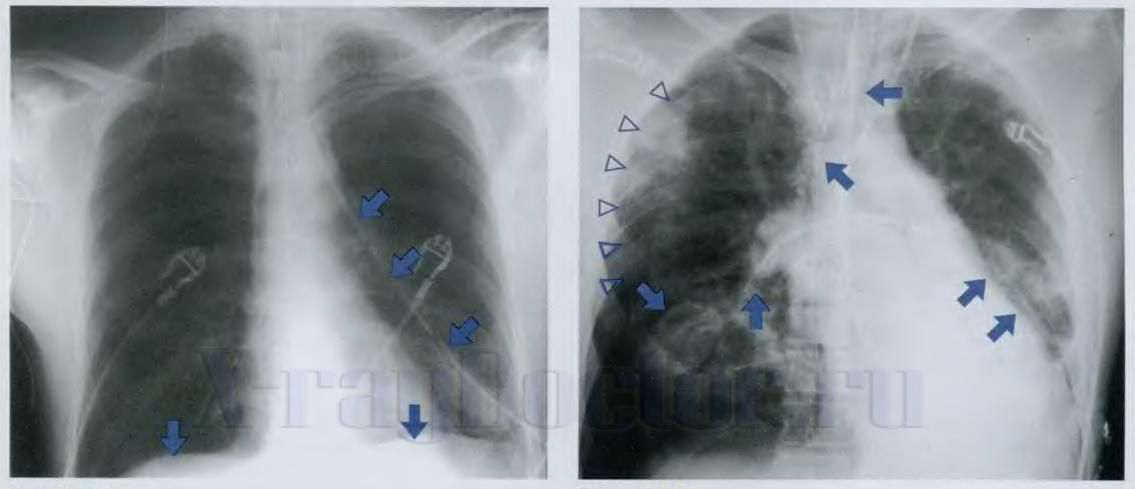

На рентгенограмме легких чаще всего выявляются шаровидные метастазы. Они представляют собой округлые интенсивные тени. При некоторых опухолях, таких как опухоль Юинга и остеогенная саркома, шаровидные образования разбросаны по всей легочной паренхиме. Специфической их особенностью является нормальный легочной рисунок. Он не деформируется вокруг аномальных затемнений. Метастазы быстро увеличиваются в размерах, но сохраняют свою форму.

Как на рентгенограмме проявляется лимфангит

Лимфангит на рентгенограмме проявляется сетчатыми, петлистыми и тяжистыми тенями, которые отходят от корней в легочную паренхиму вдоль пораженных бронхов и сосудов. Вокруг воспалительных фокусов прослеживаются мелкие треугольные тени, которые отражают спадение субсегментарных участков легкого. Если лимфангит наблюдается на фоне пневмосклеротических изменений (разрастание соединительной ткани), расшифровать изменения на рентгенограмме сложнее.

Рентгенологические признаки множественных метастазов:

- фокусные или крупноочаговые тени разбросаны по легочным полям;

- локализуются преимущественно в периферических отделах;

- мелкоочаговая диссеминация является последствием распространения раковых клеток по кровеносным сосудам;

- единичные тени встречаются редко. Они редко достигают в диаметре более 10 см;

- полости в проекции теней свидетельствуют о распаде ткани.